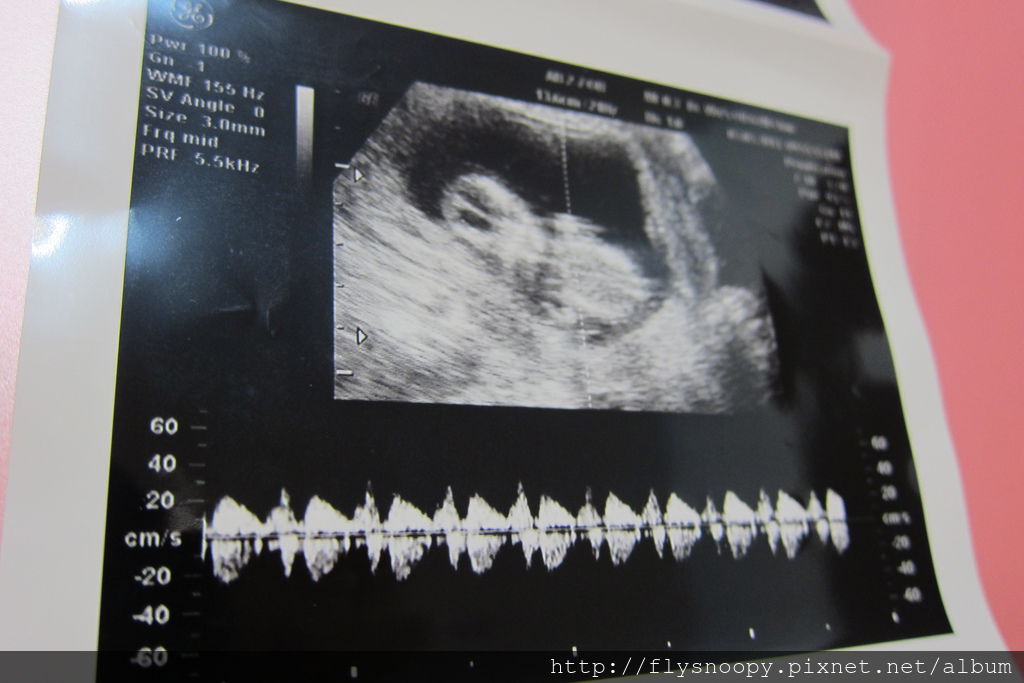

上面三張超音波照片就是這次急診時拍的

這次baby CRL 是7.01,生長一切正常,但是我還是很擔心

醫生說流血就是有流產跡象,所以開藥並要我在家臥床安胎